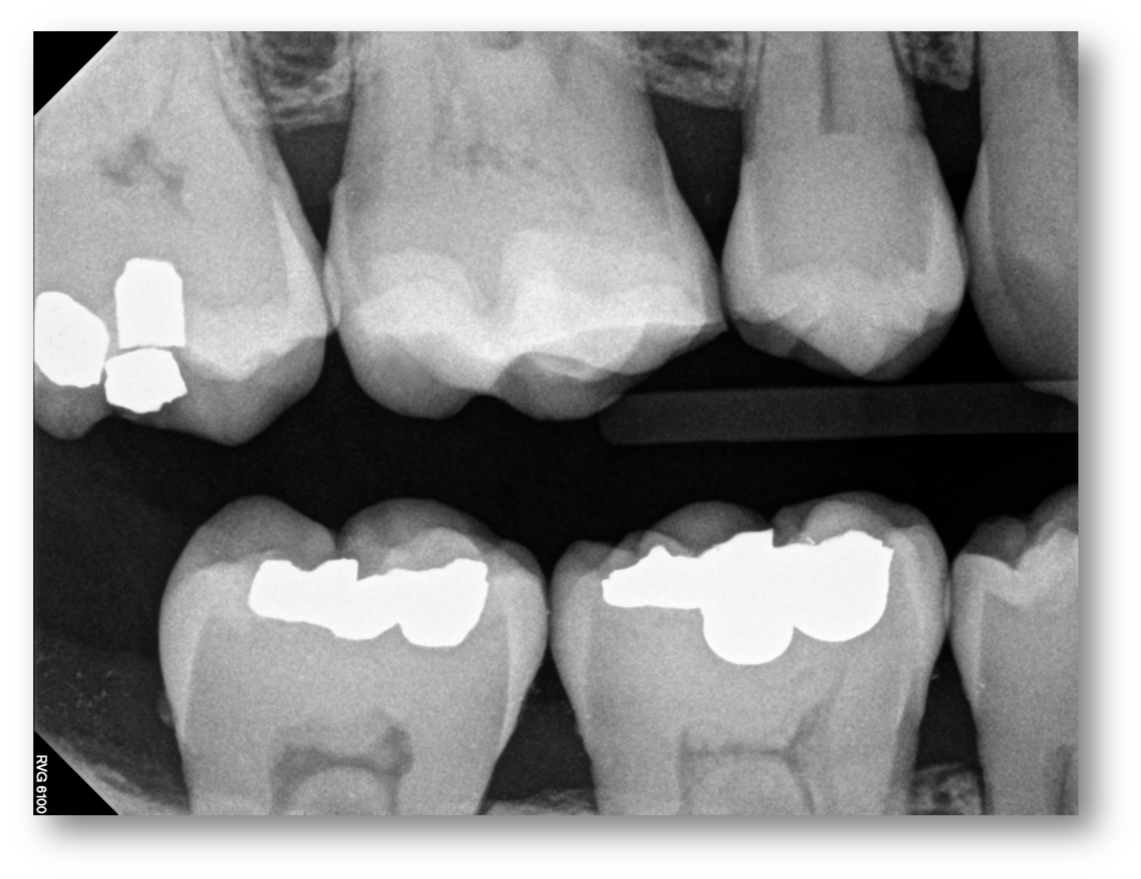

A patient with an example of cracked-tooth syndrome, seen in Figure 8, presented with thermal sensitivity, pain to bite, no periapical radiolucency, and no spontaneous pain. In general, the dentist should drill until there is no leakage around the crack: no ring or stain around the crack inside the dentin, no separation of the pieces, and no decay (Figure 9). Caries indicators may be used to guide by highlighting elements such as horizontal and vertical cracks in teeth that may otherwise go unnoticed. The preparation and procedural steps were essentially the same as in the previous examples: etching, rinsing, bonding, a layer of Giomer flow, light-curing, and then remaining materials were placed. All the materials were radiopaque and thus could easily be seen on a radiograph (Figure 10).

Fig 10. Radiopaque materials can be seen on a radiograph.

Figure 10